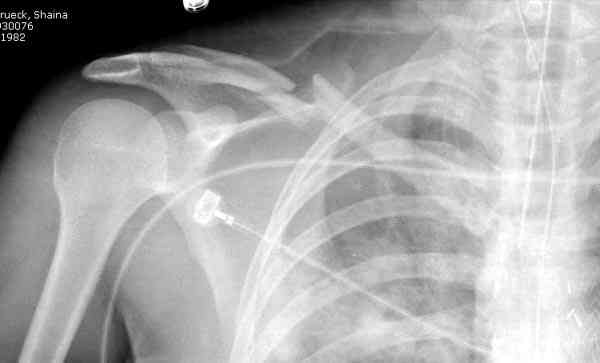

Недавно разбирали случай ложного сустава.

45 летная женщина после автоаварии, алкоголь 163 и 20 летним стажем курения.

Консервативное лечение, через 8 мес. операция Rockwood pin с костной пластикой в нашем городе другим врачом. После 8 недели падение, гвоздь удален оперирующим хирургом, больная направлена к нам. Фиксация реконструктивной пластиной с трикортикальным графтом, добавлен BMP-2. Для стабилизации фиксацию провели через акромион.

Вот уже два месяца больная также продолжает жаловаться на боли, буквально на днях удалили акромиальную часть пластины с специальной пилой с алмазным покрытием для медицинского металла. До сих пор судьба ложного сустава неизвестна....

Второй случай тоже недавно оперирован по поводу

ложного сустава, в марте травма, через 4.5 половиной

операция..